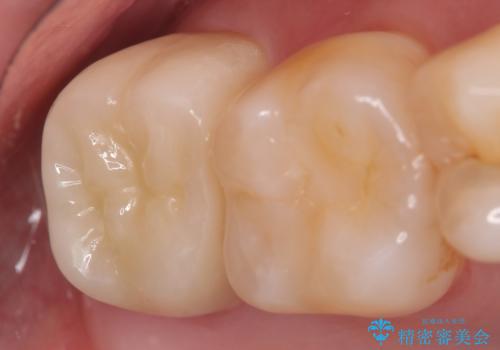

その後オールセラミッククラウンによる補綴を行いました。

今回用いたオールセラミッククラウンはジルコニアフレームという白い素材の上にセラミックを盛っているため、審美性が非常に高いのが特徴です。

また、ジルコニアは人工ダイヤモンドの材料にも使われているほど高い強度を持っており、そのためオールセラミッククラウンは審美性だけでなく、奥歯やブリッジの補綴も可能とするクラウンです。